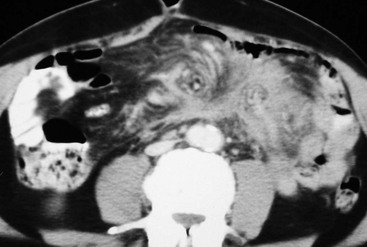

Peritoneal seeding is a common mechanism of metastatic dissemination in advanced gastrointestinal and gynaecological malignancies. Peritoneal carcinomatosis (PC) is the term given to malignant tumour seeding of the peritoneum with most common primaries being the ovarian (71%), gastric (17%) and colorectal (10%) cancers. When cancer cells from a growing primary neoplasm reach the peritoneal surface, they are carried out by the peritoneal fluid and disseminated throughout the peritoneal cavity. Distribution of disease in PC is related to peritoneal fluid circulation along predetermined anatomical routes as previously described in the section ‘Ascites’. This peritoneal fluid circulation and the areas of temporal stasis of fluid explain the distribution of peritoneal seeding. Pooling of ascites favours the deposition and growth of seeded malignant cells. The most common seeding sites include the pouch of Douglas, the distal small-bowel mesentery near the ileocaecal junction, the sigmoid mesocolon, the right paracolic gutter, the pouch of Morison and the right subdiaphragmatic area.3 In general, more aggressive neoplasms exhibit malignant peritoneal deposits closer to the primary tumour, as opposed to less aggressive neoplasms that tend to manifest deposits in remote areas in the abdominal cavity. Variable amounts of ascites may accompany peritoneal seeding but ascites is not always present. Ascitic fluid is sometimes locculated and/or septated, and therefore it may be absent in dependent areas such as the pelvis. Peritoneal deposits (Fig. 30-18) may appear as thickening or enhancement of the peritoneum, nodules or plaques on the peritoneal surfaces, masses or merely stranding of the mesenteric fat.